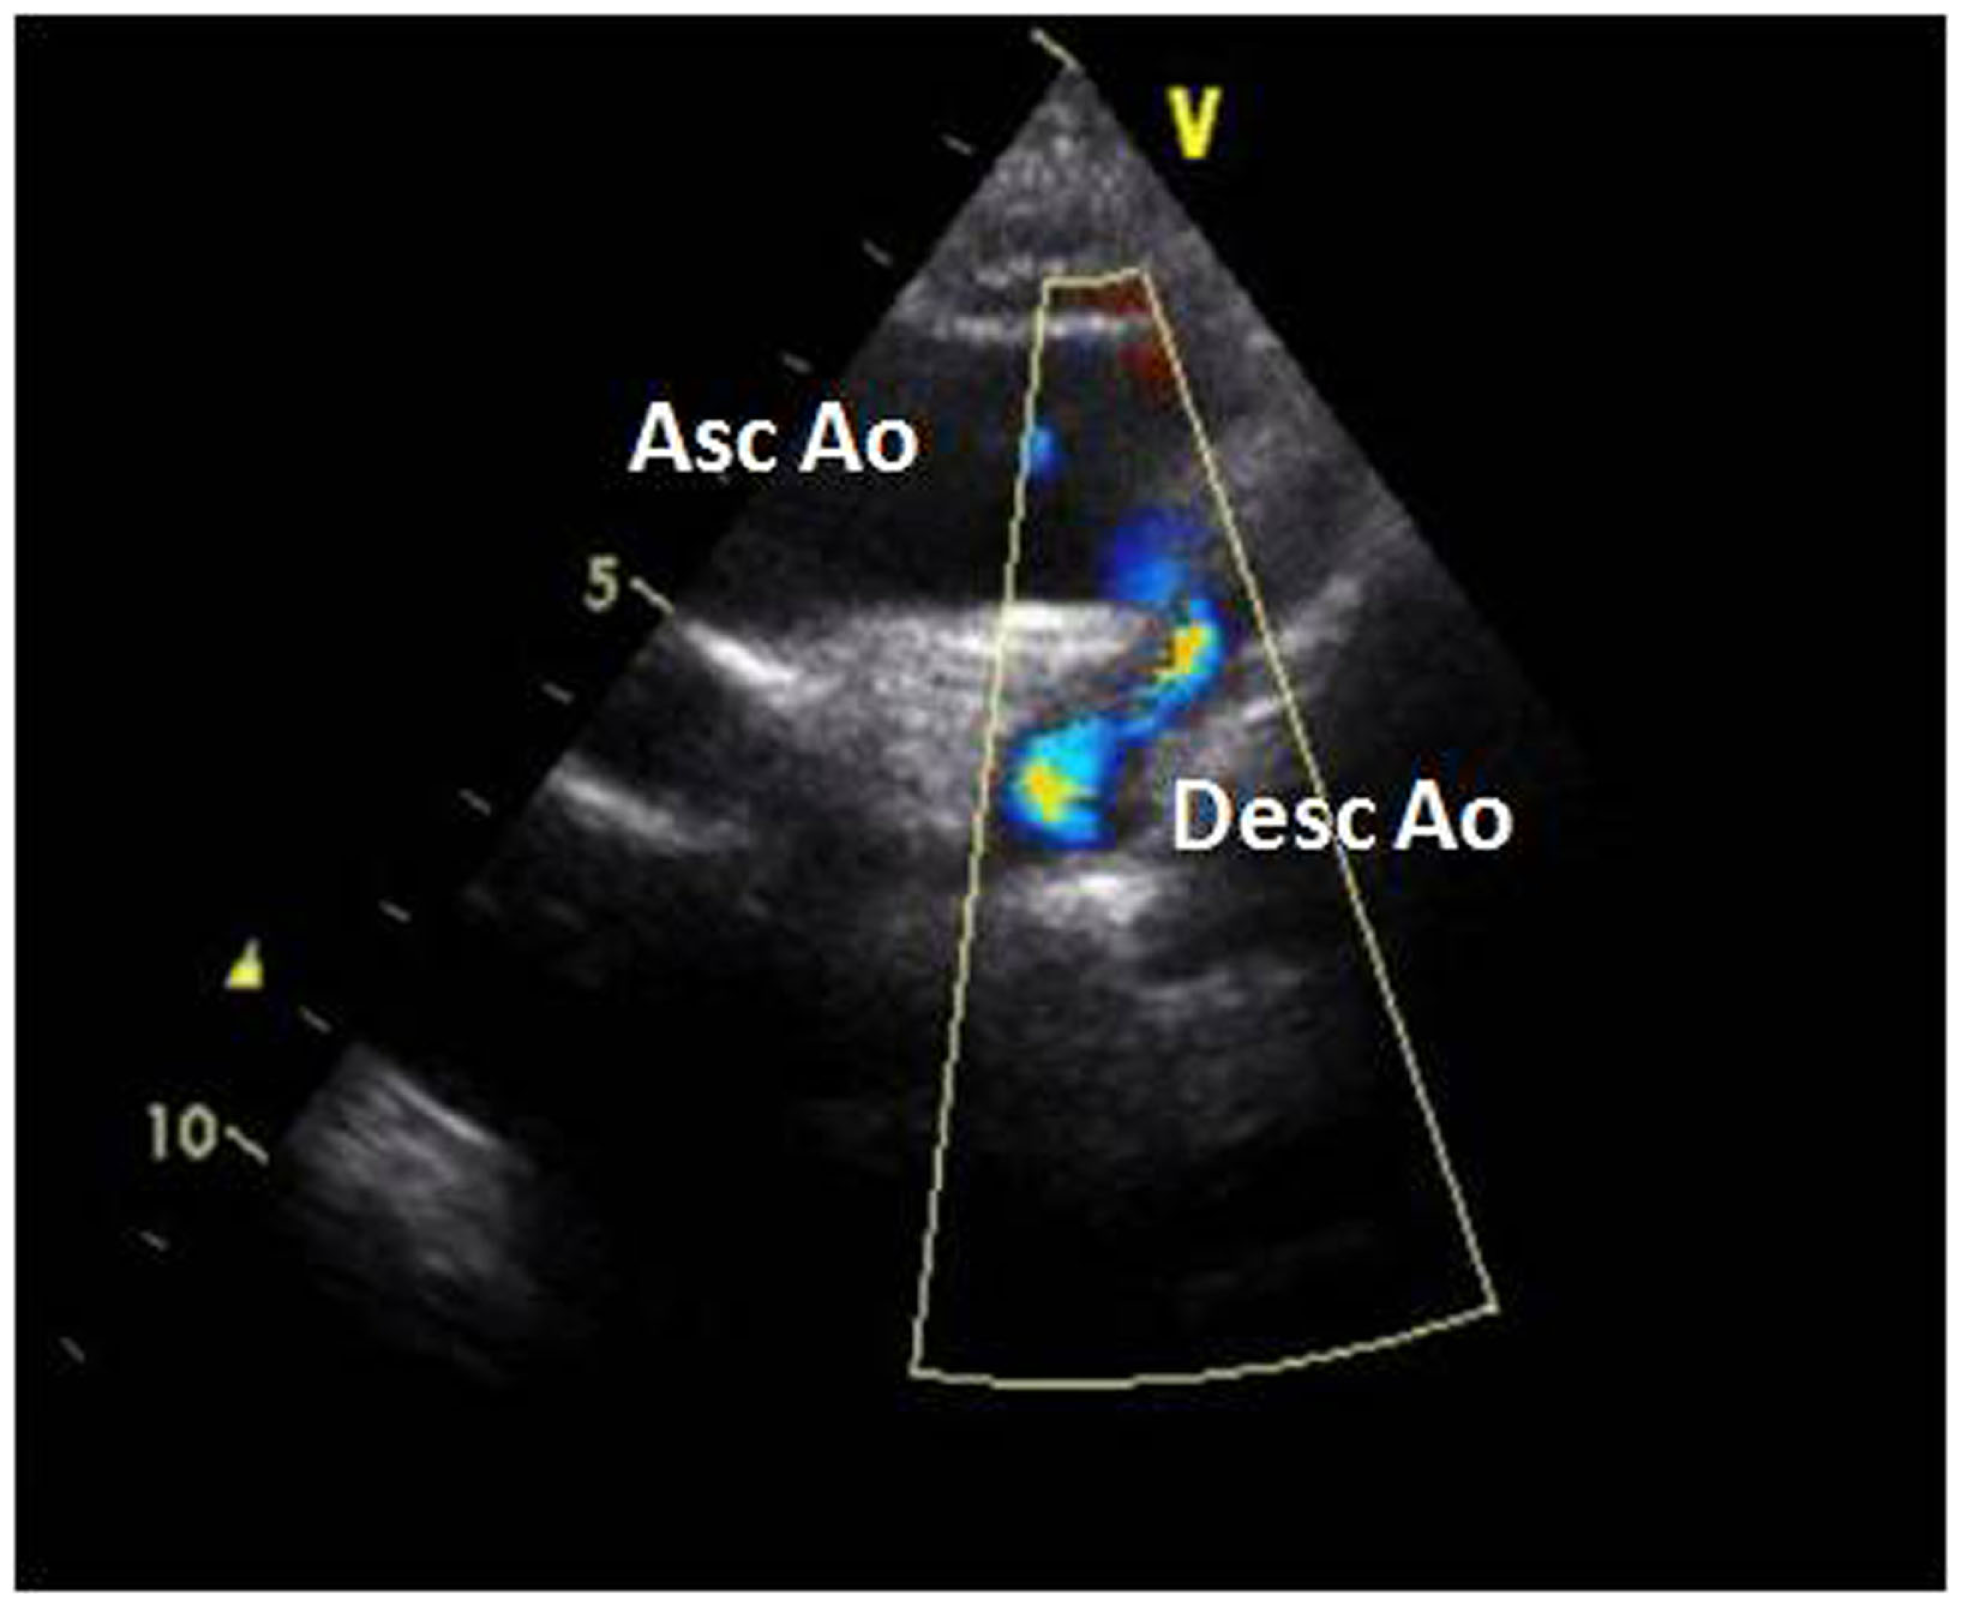

The electrocardiogram showed sinus rhythm with signs of left auricular hypertrophy, but no ventricular hypertrophy. The chest radiography (Figure 1) showed mild cardiomegaly (ICT 0.64) and an absent aortic knob, compatible with the diagnosis of coarctation. The echocardiography showed a bicuspid aortic valve (Figure 2) with severe stenosis (peak systolic gradient of 60 mmHg and mean of 30 mmHg), left ventricular hypertrophy (Z-score +3.3), preserved systolic and diastolic function (mitral E/A ratio 1.6; mitral A deceleration time 0.10 s, E/E′ 22 secondary to increased left heart filling pressure), and tortuous aortic arch with narrowing and acceleration of flow at the aortic isthmus (Figure 3). CMR with angiography showed absence of continuity between the ascending aorta distal to the left subclavian artery (Type 1) and the descending aorta, extending over 5 mm. There was a bend in the arch and diverticulum on either side of the zone of discontinuity, making the diagnosis of atresia rather than interruption of the aortic arch. There was no patent ductus arteriosus (PDA), no associated endofibroelastosis and the descending aorta was fed exclusively by massive systemic collateral circulation (Figures 4–6).

Figure 3

Suprasternal view of the aortic arch with severe narrowing of the aortic isthmus and aliasing of flow. Abbreviations: Asc Ao, ascending aorta; Desc Ao, descending aorta.